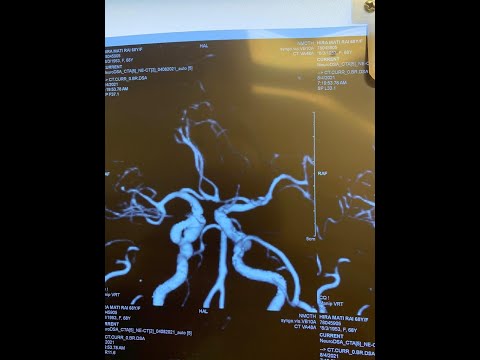

Hellow guys, Welcome to my website, and you are watching Anterior Clinoid Process | Real neuroanatomy. and this vIdeo is uploaded by Real Neuroanatomy at 2022-02-03T20:41:40-08:00. We are pramote this video only for entertainment and educational perpose only. So, I hop you like our website.